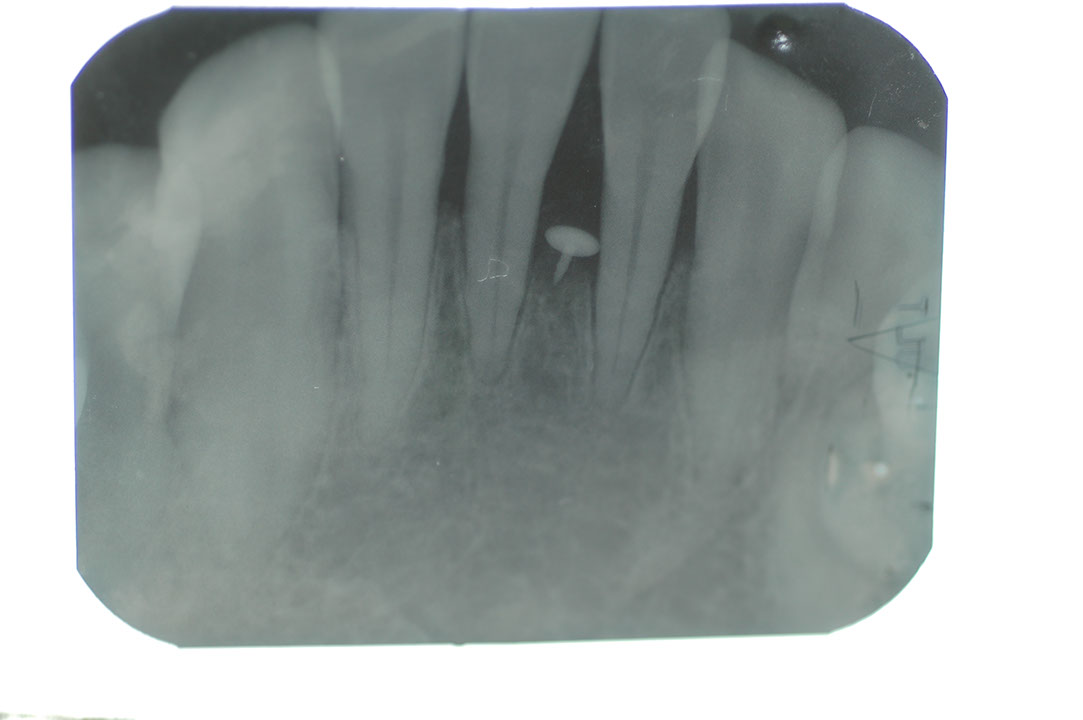

Perio 2t4.JPG

光牙醫